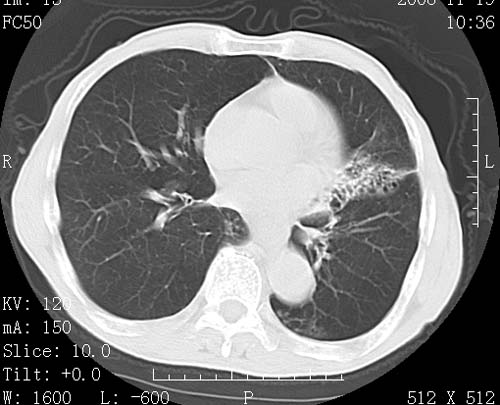

标题: CT16691:m 67 胃镜确诊食管下段及贲门癌 [打印本页]

标题: CT16691:m 67 胃镜确诊食管下段及贲门癌

术前查体,双肺部结节是转移?结核?请点评

1)符合食管癌表现。2)两肺及纵隔淋巴结多发性转移瘤。3)左肺上叶舌段及两肺下叶炎症感染。

食管癌伴双肺转移,评述:肺部毛细血管网丰富,全身血液均快速流经肺部,癌细胞容易过滤定植,形成转移瘤,影象特点为以毛细血管末梢为中心的结节灶,边缘光滑锐利,少见有中心空洞着,不同来源的转移瘤可有各自特点,如甲状腺癌为双肺弥漫性微结节,本例有原发灶,双肺影象灶典型,左肺舌段条带状网格样伴胸膜天幕征,可视为癌性淋巴管炎。